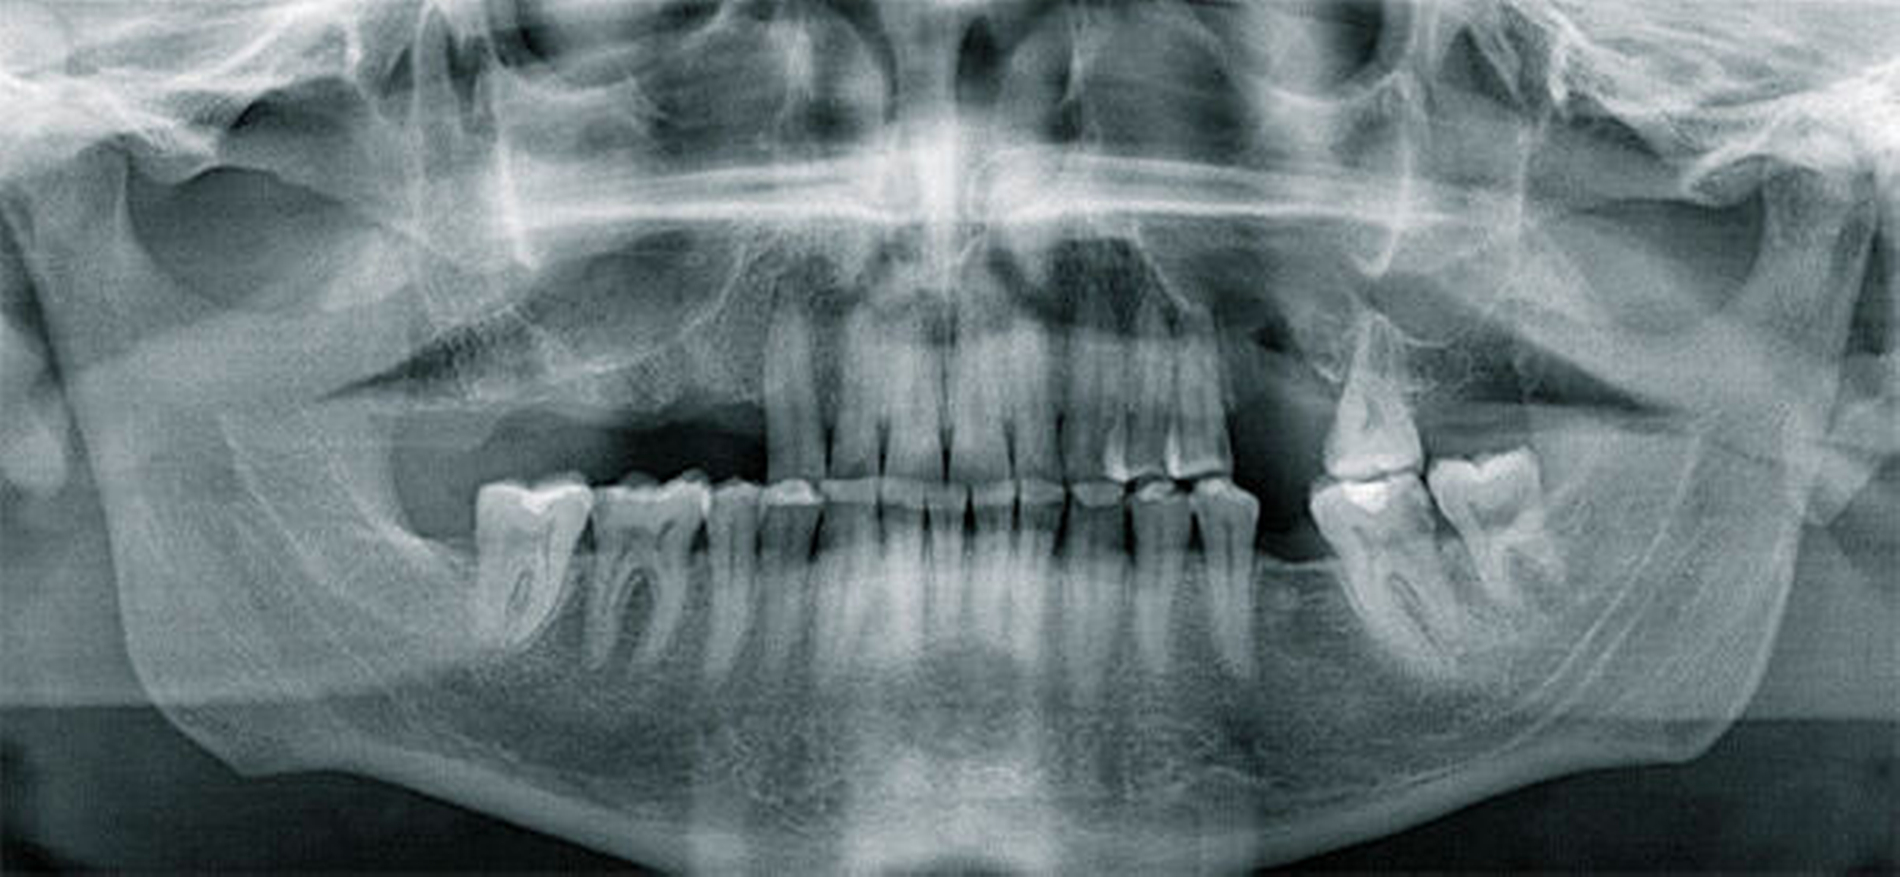

In Intubationsnarkose konnte der Fremdkörper aus dem rechten Sinus maxillaris über einen osteoplastischen offenen Zugang vestibulär regio 014 bis 015 geborgen werden (Abbildung 3). Die Mund-Antrum-Verbindung regio 026 wurde mittels eines Rehrmannlappens verschlossen. Gleichzeitig erfolgte die Entnahme von Proben aus bei den Kieferhöhlen. Die Abbildung 4 zeigt den kunststoffartigen Fremdkörper im Sinne von Füllungsmaterial. Die postoperative Röntgenkontrolle dokumentiert die Entfernung des Fremdkörpers (Abbildung 5) in toto.

Ein anschließendes Gespräch mit dem Patienten konnte nicht klären, wie das Füllungsmaterial in die Kieferhöhle gelangt ist. Histologisch ergab sich entzündungsbedingt eine beidseitig polypöse, ödematöse Kieferhöhlenschleimhaut. Am dritten postoperativen Tag entließen wir den Patienten bei sanatio per primam intentionem in die ambulante Nachsorge.